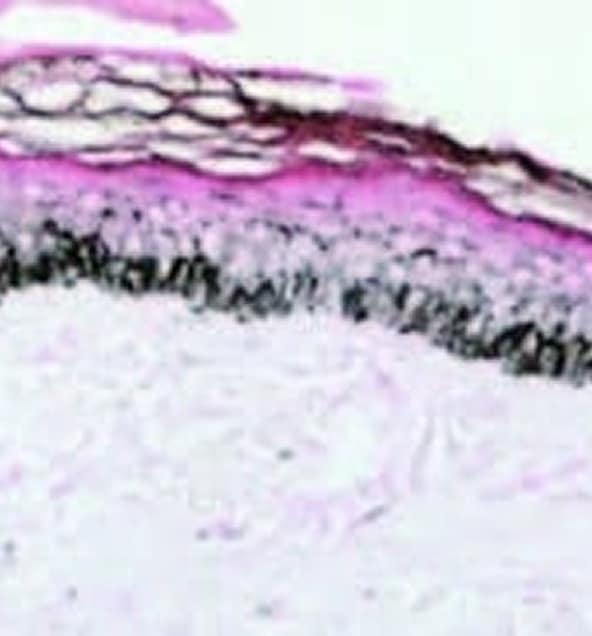

REDUKTION DER EPIDERMALEN MELANINDICHTE 1 WOCHE NACH MIKRONEEDLINGVERFAHREN

- Induktion von Keratinozytenfluktuation und „Wiederherstellung“ der normalen Pigmentaktivität der Melanozyten in überpigmentierten Bereichen.

- Dies geschieht in der dermal-epidermalen Junktionszone (DEJ).

- Dieser Dermisbereich mit flacher DEJ ist die Zieltiefe für die Mikronadel. Siehe Pfeile, wo die Mikrokanäle gebildet werden